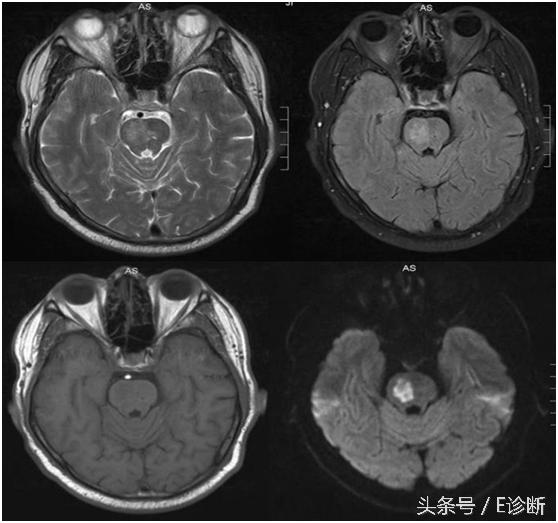

左侧基底节区急性期脑梗死,发病24小时,T1WI为稍低信号,T2WI及flair像为稍高信号,DWI为高信号,MRA示左侧大脑中动脉闭塞,此时头CT未见异常改变。